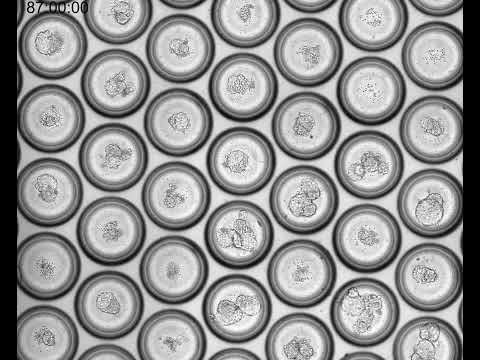

Fueyo and her team used a ball of stem cells induced to mimic a blastocyst, the phase of embryonic development about five days after fertilization. This 3D model, or blastoid, replicates the developmental stage just before the embryo implants into the uterus’s lining.

When the researchers disabled a group of remnant virus genes known as LTR5Hs, the embryonic model either turned into a disorganized clump of cells or died. Without the LTR5Hs, the middle layer (epiblast) of the three-tissue-layered blastoid did not form properly.